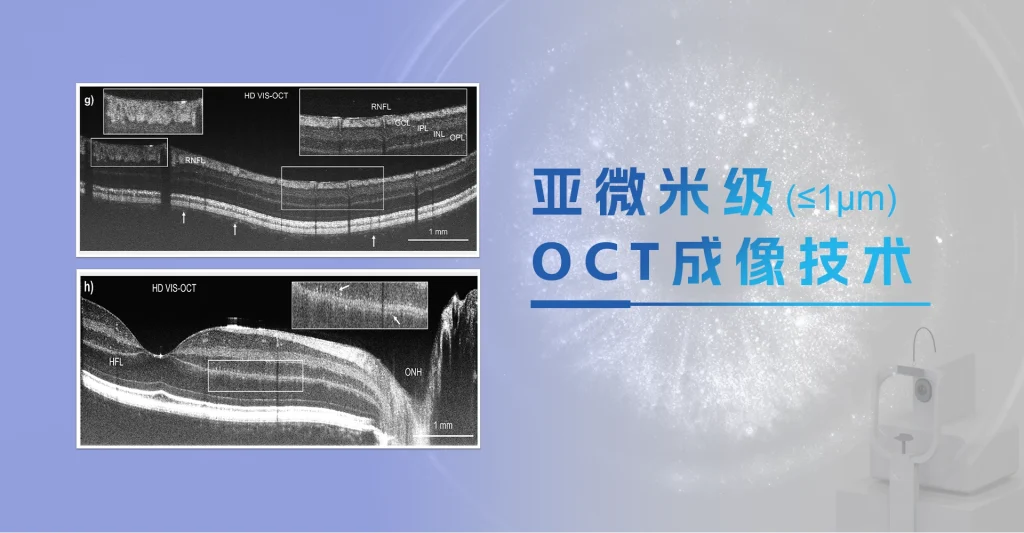

• 结构 OCT 轴向光学分辨率3.8μm